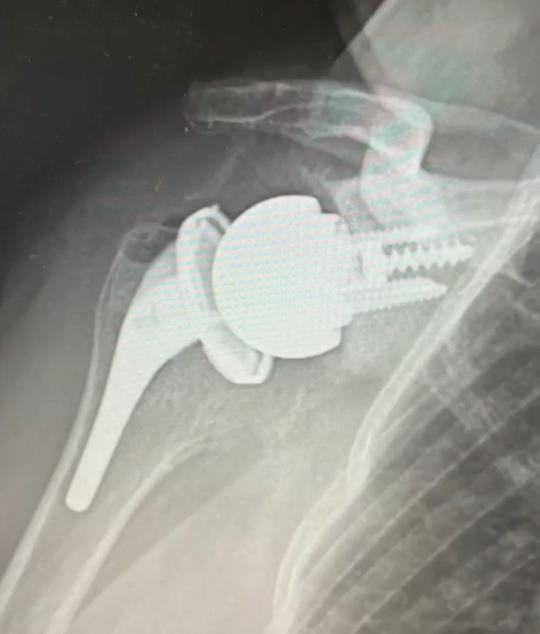

InSet™ Reverse Total Shoulder Arthroplasty

• InSet™ Reverse Shoulder System is a non-constrained reverse glenohumeral prosthesis intended for total shoulder replacement, comprising a humeral stem, modular tray, UHMWPE bearing, glenoid baseplate, locking/set screw, compression screw, supplementary screws, and a metal glenosphere.

• Components: humeral stem, modular tray, UHMWPE bearing, glenoid baseplate, locking nut/set screw, compression screw, supplementary screws, and metal glenosphere.